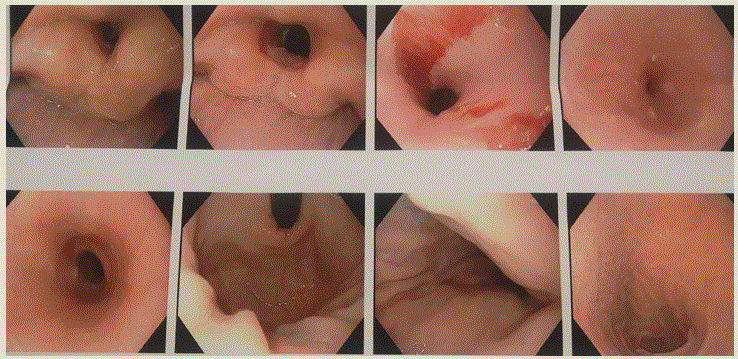

Inició padecimiento actual desde hace 1 año con disfagia progresiva de sólidos a líquidos. Recibió tratamiento con omeprazol y antimicrobianos. Se realizó una primera endoscopia en donde se encontró resistencia al paso del endoscopio, lográndose romper una membrana por debajo del cricofaríngeo con el paso del mismo. Hace 2 meses se agregó odinofagia, motivo por el que acudió a consulta con otorrinolaringólogo quien indicó dexametasona, procinéticos, omeprazol y complejo B. Por persistencia de la sintomatología, acudió a la consulta de gastroenterología con nueva panendoscopía que reportó una membrana por debajo del cricofaríngeo, que causaba resistencia, lográndose romper dicha membrana con el paso del endoscopio, observando 2 desgarros superficiales de la mucosa, sin sangrado ni perforación. El resto de la mucosa del esófago era normal, la unión esófago gástrica a 37 cm de la arcada dental superior y coincide con la plicatura diafragmática que estaba a 37 cm de la misma sin hernia ni esofagitis (figura 1). En la exploración física fue notable la palidez conjuntival, queilitis angular, fisuras labiales leves, así como dificultad para la apertura bucal (figura 2); uñas pálidas con tendencia a la coloración amarillenta, quebradizas (figura 3).

Imagen: Zapata et al.

Membrana en el tercio superior del esófago, por debajo del cricofaríngeo. Desgarro superficial de la mucosa al paso del endoscopio.

Figura 1 Panendoscopía